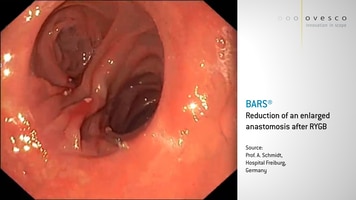

Lumenreduktion für die bariatrische Endoskopie

Einsatzgebiet des BARS®

BARS® ist ein System zur endoskopischen Behandlung von Gewichtszunahme oder Dumping-Syndrom nach einem Magenbypass.

2Quelle: Prof. A. Schmidt, Universitätsklinikum Freiburg, Deutschland